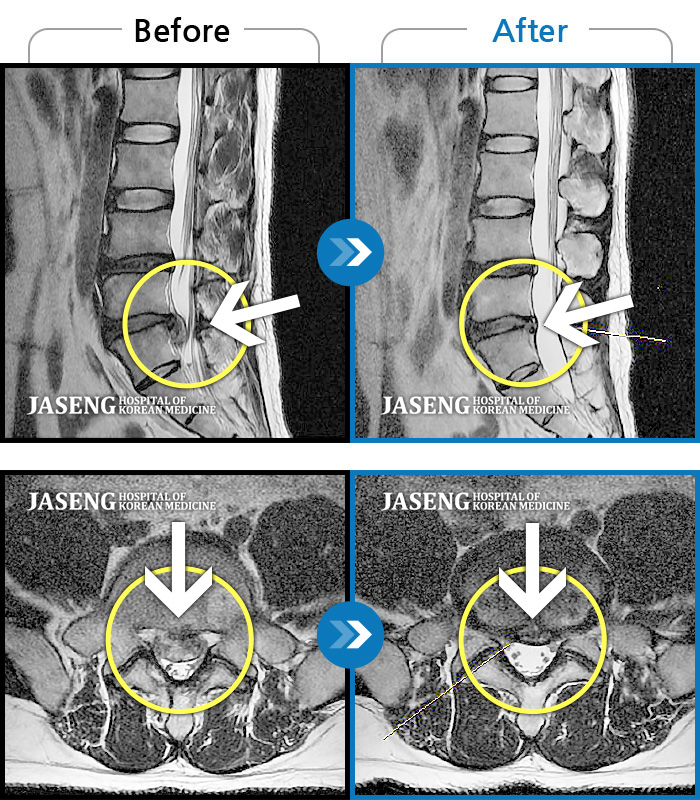

Before

After

환자에게 사전 동의를 받아 동일 조건에서 촬영되었습니다.

개인에 따라 치료 후 부작용이 발생할 수 있으니 의료진과 상담 후 치료를 진행하시기 바랍니다.

운전 후 갑자기 통증과 다리저림이 심해져 거동이 안될 정도였습니다.

양측 허리에 묵직한 통증과 양측 허벅지부터 종아리까지 하지 방사통